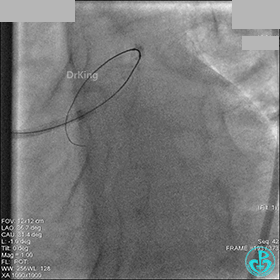

1周后再次上台,右冠脉3级血流,3段局限性严重狭窄,内膜模糊,应该是上次操作夹层遗留下的血肿。

先处理前降支开口严重狭窄并顺利植入前降支到左主干支架。